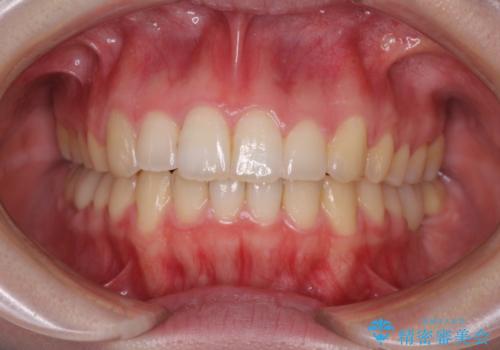

気になる部分を全て治療 総合歯科治療で口腔内環境改善

総合歯科治療 矯正治療と失活歯のセラミック補綴治療